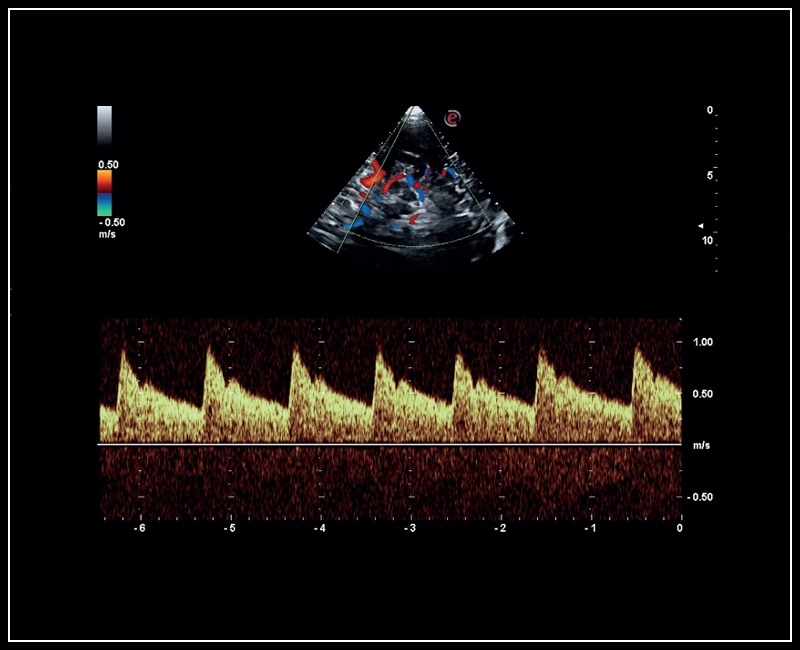

MyLab™C30 - Polm - Doppler

MyLab™C30 - Polm - Doppler

Q7 - Doppler

Q7 - Doppler